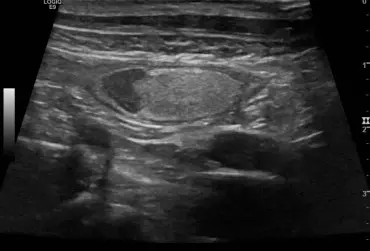

Zespół gruczolakoraka torbielowatego nerek i guzków włóknistych skóry u owczarka niemieckiego – opis przypadku

U 8-letniego niekastrowanego owczarka niemieckiego wykryto obecność kilku guzków skórnych widocznych na kończynach i na nosie. Badanie cytologiczne nie było jednoznaczne. W badaniu histopatologicznym jednego z usuniętych guzków stwierdzono obecność masy kolagenowej z niewielką ilością komórek zajętych głębokim, ropnym zapaleniem skóry. Po roku wykonano badanie ultrasonograficzne układu moczowego z powodu krwiomoczu i pogorszenia się stanu ogólnego psa. Wykryto liczne torbiele w obu nerkach o nietypowej strukturze. Na podstawie wyników badań postawiono rozpoznanie zespołu gruczolakoraka torbielowatego nerek i guzków włóknistych skóry (ang. renal cystadenocarcinoma and nodular dermatofibrosis – RNCD).